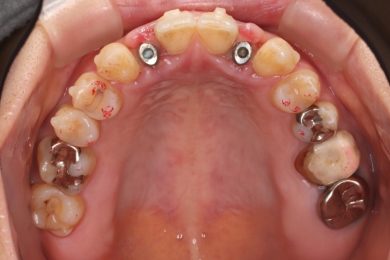

先天性欠如による上顎前歯欠損部にインビザライン術前矯正とインプラントを埋入した症例

初診時・インプラント・終了時